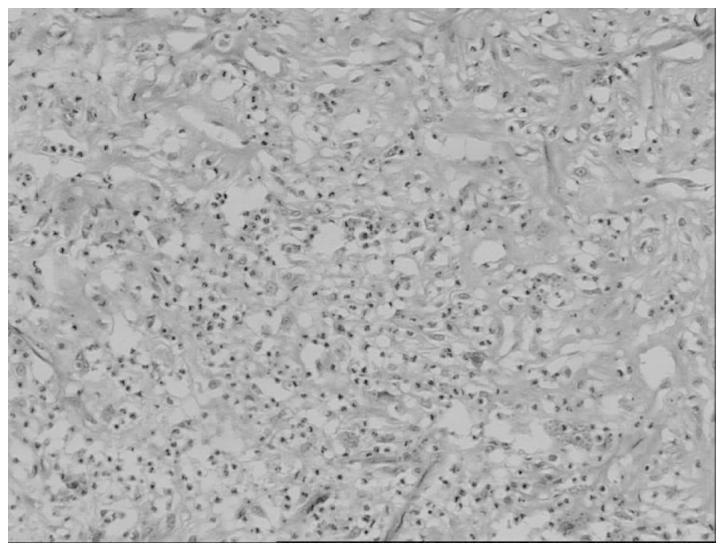

Multiple mesenteric well-differentiated (WD) liposarcoma is an extremely rare entity. The present study describes a case of multiple mesenteric WD liposarcoma, complicated by purulent inflammation, in a 59-year-old male who presented with abdominal pain and pyrexia of unknown origin. A computed tomography scan of the abdomen revealed a large, non-encapsulated mass in the abdomino-pelvic cavity, which was characterized by two components, a main portion of fatty density and a non-adipose solid portion. A re-evaluated CT scan, performed eight days later, revealed an enlargement of the non-adipose mass. A laparotomy was performed, and numerous separated fatty nodules and masses of various sizes were identified within the mesentery of the small intestine. The histological findings were consistent with an adipocytic subtype of multiple mesenteric WD liposarcoma, with the largest of the tumors complicated by purulent inflammation. The multiplicity of these tumors and the concurrent purulent inflammation in the present case make it unique.